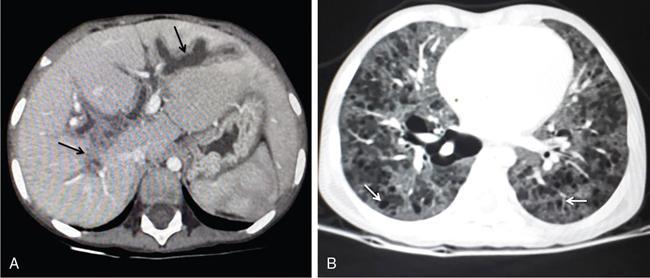

DIFFUSE PARENCHYMAL DISEASES OF THE LIVER Ishan Kumar, Ashish Verma The hepatic parenchyma is the site for multiple essential, interrelated, and complex metabolic activities to assimilate nutrients, detoxify the body, and synthesize vital molecules such as enzymes, hormones, cofactors and essential components of the coagulation pathway. The chemical reactions involved in each of these activities pose a threat to the hepatocytes, which may be damaged leading to the initiation of reparative processes. Further, the liver, being a highly vascular organ with multiple metabolic activities, is liable to be involved in many systemic vascular and metabolic disorders. On one hand, such changes cause healing of the tissue injury, but on the other hand, lead to diffuse parenchymal changes, which may result in suboptimal functioning of the organ. Such a condition is labelled as ‘diffuse liver disease’ and includes (a) diseases caused due to storage of certain chemical products of such chemical reactions labelled as ‘storage disorders’, (b) diseases caused due to reduction of blood flow to the organ, (c) parenchymal injury due to stasis of bile at various levels in the pathway due to varied causes, and (d) involvement of liver in systemic or organ-based inflammatory disorders. The mainstay of diagnosis of diffuse liver diseases is the detection of alterations in the biochemical parameters in blood indicative of liver function, which however is nonspecific to various aetiologies. The diffuse liver diseases in children are quite different from those in the adult population and constitute mainly of congenital or inherited metabolic and vascular diseases as opposed to diseases of acquired aetiologies in the latter population. The gross and microscopic pathological changes are accordingly different in the paediatric population and may be utilized to add specificity to the biochemical indicators as far as aetiological diagnosis is concerned. The invasive and potentially hazardous sampling mandated for histological evaluation of liver parenchyma has been replaced by an array of imaging modalities in recent times. The present chapter presents a review of the currently available imaging modalities (viz. cross-sectional imaging modalities such as ultrasonography, computed tomography [CT] and magnetic resonance [MR] imaging) for evaluation of diffuse liver diseases along with the pertinent imaging features and guidelines for their rational use in various indications. Also a short review of certain key technical and technological details is included. Jaundice and hepatomegaly are the most common clinical manifestations of liver disease. Anorexia is a nonspecific sign, often present in acute or chronic liver disease. Jaundice is a sign of increased bilirubin content in the blood, that can exist in four forms: (i) unconjugated bilirubin bound to albumin, (ii) unbound unconjugated bilirubin, (iii) conjugated bilirubin and (iv) δ fraction. Direct fraction includes both conjugated bilirubin and δ bilirubin. Conjugated hyperbilirubinemia is due to decreased excretion by liver or biliary tract obstruction. Pruritus, spider angioma on face and neck, ascites, portal hypertension, botchy palmer erythema, subcutaneous xanthoma, gastrointestinal (GI) variceal bleed, encephalopathy, renal dysfunction and pulmonary involvement are manifestations of advanced cirrhosis. Evaluation of total serum bilirubin and its fractional analysis into indirect (unconjugated) and direct (conjugated and δ fraction) bilirubin helps to distinguish between elevation caused by haemolysis and that due to hepatic dysfunction or biliary obstruction. Elevations in alkaline phosphatase (ALP), 5′ nucleotidase, and γ-glutamyl transpeptidase (GGT) levels are an indicator of biliary obstruction. However, it should be noted that normal growing children have significant elevations of serum ALP activity. AST (aspartate aminotransferase) and ALT (alanine aminotransferase) are significantly raised in acute hepatitis. ALT rise disproportionate to AST rise is seen in viral hepatitis. A predominant rise in AST is seen in echovirus infection, various metabolic diseases or alcohol-induced hepatitis. These aminotransferases are also elevated in NAFLD/NASH. ALT/AST rise is less marked in chronic liver disease. PT-INR, serum albumin levels can evaluate the hepatic synthesis function. Hypoalbuminemia suggests a bad prognosis. γ-Globulin is elevated in autoimmune hepatitis (AIH). Alpha-fetoprotein is raised in hereditary tyrosinemia or hepatic neoplasms. Indications of liver biopsy in the paediatric age group include neonatal cholestasis, metabolic liver disease, NAFLD, congenital hepatic fibrosis, abnormal biochemical liver tests of unknown aetiology, intestinal failure associated liver disease, acute liver failure and liver tumours. Although biopsy of children and infants is considered a safe procedure, due to incidences of shock, the North American Society for Pediatric Gastroenterology and Nutrition (NASPGHAN) has recommended liver biopsy in children not to be necessarily performed as outpatient procedures. Sonography-guided percutaneous liver biopsy has been reported to be safer, more efficient, more comfortable and only marginally more expensive than blind biopsy. The use of coaxial technique, determination of the number of passes and use of track embolization were at the discretion of the interventional radiologists. In cases of uncorrected PT-INR elevation, transjugular liver biopsy can be performed. Ultrasound (US) is a valuable tool in the diagnosis and management of diffuse liver diseases. It provides useful information about the size, surface, parenchymal architecture, biliary channels and blood flow of the liver. US examination of the liver is performed in the supine position with a convex (5–7.5 MHz) probe. High-frequency (7.5–12 MHz) linear transducers can be used in young infants because of their small size. US examination can be completed with the colour Doppler technique and US elastography, if needed. CT protocol typically requires image acquisition during the multiple phases with a slice thickness of 5 mm or less and a pitch ranging from 1 to 1.5. Contrast injected is 2 mL/kg through manual or mechanical injection. The arterial phase begins at 10–15 seconds and the portal phase is at 20–40 seconds after contrast injection. Equilibrium phase is obtained at 3 minutes, when needed. MRI protocol to evaluate paediatric liver chiefly includes free-breathing sequences, due to the challenge offered by an inadequate breath-hold in these patients. Due to the same reason, motion insensitive single-shot HASTE sequences or motion insensitive T1-weighted spoiled GRE single-shot sequences are also widely utilized in paediatric MR examinations. In slightly older children with a relatively uniform breathing pattern, external trigger signals from a breathing belt, or navigator techniques may be used to overcome motion artefacts from breathing. T1- and T2-weighted turbo spin-echo (TSE) sequences and T2-weighted single-shot sequences in axial and coronal planes are initially acquired to evaluate the anatomy and screen for pathologies. This is followed by a gradient echo (GRE) images to examine vascular structures. Multiecho images with T1-weighting can be acquired to evaluate the fat content of lesions. Contrast-enhanced MRI with intravenous injection of gadolinium (Gd)-based contrast agent is performed as routine in cases with suspected portal hypertension or in any associated suspected neoplastic lesion. This is usually clubbed with MRA for vascular mapping. Arterial phase and portal phase should be acquired 10–15 seconds and 20–30 seconds, respectively after the start of contrast agent injection. GRE T1-weighted sequence should be repeated continuously four or five times to include achieve all phases of liver perfusion. Finally, steady-state imaging should be performed in the equilibrium phase (3 minutes) using T1-weighted and T1-weighted fat-suppressed imaging sequences. MRI contrast media should be administered with caution after evaluation of eGFR, and is safer than the iodinated contrast media needed for CT scan examination, and is hence preferred. Liver size measurement is commonly obtained in one of the two ways (a) an anterior to the posterior measurement of the liver in the midclavicular line, (b) a dome-to-tip longitudinal measurement of the liver in the midclavicular line. Table 9.8.1.1 provides suggested upper limit values of liver and spleen length for various paediatric age groups. Despite advances in 3D US, volume measurements of liver size have not been incorporated in the routine clinical practice because it is time-consuming, requires considerable skill and technically difficult fusion of multiple 3D sweeps. Nonalcoholic fatty liver disease (NAFLD) is referred to as triglyceride accumulation in hepatocytes and encompasses a broad range of clinicopathological entities ranging from simple steatosis, steatohepatitis to cirrhosis. Its worldwide reported prevalence is approximately 2.6%–10% in the general paediatric population and as high as 38% of obese children under the age of 19 years. In India, the reported prevalence is as high as up to 22% in the general paediatric population and up to 45% in obese and overweight children. Hepatic steatosis currently is the most common cause of chronic liver disease in paediatric patients. Table 9.8.1.2 highlights the causes of hepatic steatosis in paediatric age group. The pattern of injury is similar to alcoholic liver disease. Nonalcoholic steatohepatitis (NASH) constitutes a subset of NAFLD, ranging from simple steatosis to inflammation and fibrosis. NASH in children has two distinct histological subtypes. Type 1 NASH resembles adult subtype with macrovesicular steatosis, lobular inflammation, and ballooning degeneration and perisinusoidal fibrosis. Type 2 NASH shows steatosis with portal fibrosis and is present in younger children with increased severity of obesity. ALT can be normal in 20% of the patient with NAFLD and liver biopsy is the gold standard for diagnosis as well as a semiquantitative assessment of disease severity. In clinical practice, the diagnosis and monitoring of NAFLD largely rely on ultrasonography. Grade I fatty liver refers to diffusely hyperechoic parenchyma with a well-visualized diaphragm (Fig 9.8.1). Bright liver with loss of periportal echogenicity and indistinctly visualized vessels is referred to as grade II and blurring of the diaphragm is classified as grade III fatty liver. Limitations of the US are lack of objective quantification and diminished sensitivity in cases where biopsy-proven steatosis ratio is less than 30%. Moreover, hepatic fibrosis and inflammation in cases of NASH are sonographically indistinguishable from simple steatosis. Contrast-enhanced US can diagnose the presence of fibrosis in NAFLD, which is evident from the decreased accumulation of microbubbles in the liver parenchyma. The distinction between hepatic steatosis and fibrosis is important clinically, as fibrosis can progress to cirrhosis if left untreated. US elastography has emerged as a promising technique to screen the children with NAFLD to look for ongoing steatohepatitis/fibrosis. Transient elastography is the most popular elastography technique which has shown excellent accuracy in the adult population with chronic hepatitis. However, its accuracy in NAFLD is significantly lower and the data of effectiveness in the paediatric population is limited. Acoustic radiation force impulse imaging (ARFI) has been shown to have a good correlation with AST/ALT ratios in obese children with NAFLD. An ARFI elastography value of >1.19 m/s predicts NASH-related hepatic changes in these patients while a value >1.75 m/s is suggestive of cirrhosis. Another study on shear-wave elastography has shown a high correlation in paediatric NAFLD patients with biopsy-proven hepatic fibrosis. A value of >5.1 kPa strongly predicts the presence of fibrosis whereas a value of >6.7 kPa is suggestive of stage ≥F2 fibrosis (Brunt scoring system). CT is a common modality utilized for assessment of hepatic pathologies, however is seldom used for assessment of NAFLD because of the risk of ionizing radiation. On noncontrast CT, liver attenuation <40 HU or hepatic attenuation 10 HU lesser than that of the spleen is considered as a sign of steatosis. Recent literature advocates the utilization of MRI in the evaluation of NAFLD. Fat imparts high signal intensity to the liver parenchyma on T1-weighted spin-echo MR images while it is mildly hyper- to hypointense on T2-weighted images. Conventional spin-echo imaging is relatively insensitive to mild-to-moderate fatty infiltration of the liver. The most commonly employed technique for detection of steatosis is chemical shift imaging (Dixon technique or dual-echo method) which utilizes two sets of gradient-echo images of the liver, that is in-phase and out-of-phase. On in-phase echo-time, water and fat signals add whereas, on out-of-phase echo-time, water and fat signals cancel each other. In nonfatty livers, the signal intensity of the liver parenchyma is unchanged between in- and opposed-phase images whereas a fatty liver shows a notable reduction of signal intensity on the opposed-phase images. Iron deposition in the liver can interfere with the assessment of steatosis. MR spectroscopy has been one of the most reliable techniques for the evaluation of hepatic steatosis (Fig 9.8.1.2). Protons in water molecules resonate at 4.7 ppm while that in triglyceride molecules resonate predominantly at 1.3 ppm. Other smaller lipid peaks can be obtained at 0.9, 2.0, 2.2 and 5.3 ppm. In a healthy nonfatty liver no triglyceride peak should be present. The presence of fat can allow measurement of area under water peak versus area under fat peaks to procure hepatic fat fraction. Proton density fat fraction (PDFF) measurement by MRI is another promising objective technique for quantification of steatosis in the paediatric patient. PDFF is the ratio of the density of mobile fat protons and the total density of protons including that from triglycerides and mobile water. Magnetic resonance elastography (MRE) is suggested as a noninvasive tool to evaluate liver stiffness that correlates with the degree of fibrosis. The technique is based on measuring the propagation of shear waves through liver parenchyma. A cut-off value for liver stiffness of 2.27 kPa has been suggested to predict Ludwig grade 2 or higher fibrosis. The technique depends on measuring the propagation of shear waves through the hepatic parenchymal fibrosis and differentiation of low-grade fibrosis from high-grade and also it may be feasible to distinguish steatosis from steatohepatitis. Success rate and accuracy of MRE is higher than US-based transient elastography. Cirrhosis is referred to as diffuse end-stage chronic liver disease characterized histologically by fibrosis and nodular regeneration, along with the disorganization of liver architecture. Although various underlying aetiology can lead to cirrhosis in children (Table 9.8.1.3), the most common causes in India are posthepatitic cirrhosis, Wilson’s disease (WD), AIH, biliary cirrhosis, biliary atresia and other metabolic diseases. In 5%–15% cases, the cause of cirrhosis may remain undetermined and is known as cryptogenic cirrhosis. Imaging is central to the diagnosis and management of children with cirrhosis (Fig 9.8.1.3). The role of imaging extends from diagnosis of cirrhosis to identification of complications and detection and characterization of nodules in cirrhotic liver. The imaging findings consist of changes in liver morphology, parenchyma and contour of the liver, vascular changes including portal hypertension, liver nodules and other complications of cirrhosis. Cirrhosis can lead to volume redistribution, which can be evaluated using either the US, CT, or MRI. Signs of early cirrhosis are atrophy of the segment IV, evident on imaging by increased fat segment IV and portal vein and between segment IV and left lobe. Signs of advanced cirrhosis are atrophy of the right lobe and segment IV with compensatory hypertrophy of left lobe and caudate lobe and fatty expansion of GB fossa. In some patients, a sharp notch is seen in the posterior surface of the liver (segment VI/VII). Some aetiology of cirrhosis may have different patterns of volume redistribution such as atrophy of left lobe and posterior segments in primary sclerosing cholangitis, diffuse hypertrophy in primary biliary cirrhosis, and absence of caudate hypertrophy in WD. The US can detect changes in liver segmental volumes based on linear measurements. C/RL (caudate/right lobe) ratio >0.65 calculated by comparing the transverse length of caudate and right lobe at the portal bifurcation, is a sign of cirrhosis. CT/MRI-based segmental volumetric analysis can reflect the morphological changes more effectively. Liver parenchyma in children appears as isoechoic to hypoechoic compared to the renal cortex in the US. The neonatal liver may reveal a bright echotexture. Hyperechoic parenchyma is seen in the fatty liver or liver fibrosis. Cirrhosis is seen as coarse and heterogeneous parenchyma. The liver surface in normal children appears as a hyperechoic, straight and regular line. The liver surface with diffuse irregularity or nodular surface is present in cirrhosis. CT and MRI in frank cirrhosis can reveal heterogeneous parenchyma along with the irregular surface. Diagnosis of early cirrhosis and fibrosis cannot be reliably made by the US where parenchyma may appear within normal limits. Similarly, CT and conventional MR sequences are also insensitive in early cirrhosis although early fibrosis can be seen as T1 hypointense/T2 hyperintense areas on MR and may show subtle enhancement. These T2 hyperintensities can be present as perilobular bands, perivascular cuffing, bands surrounding regenerative nodules, patchy fibrotic areas, or diffuse reticulation (honeycomb pattern). The role of US elastography and MR elastography is increasing in paediatric liver diseases for the detection of fibrosis and early cirrhosis and has been discussed in the previous section. US examination should be complimented with Doppler of the portal vein and hepatic veins if US features are suspicious of cirrhotic or fibrotic changes. The diameter of the portal vein increases with age. The mean diameter of the portal vein is 3.5 mm in children <5 years, 6.3 mm in 6–12-year old children, and 7–11 mm in >12-year-old children. Portal vein diameter is increased in portal hypertension; however, no reliable age-dependent cut-off values exist for the PV diameter in the diagnosis of portal hypertension in paediatric patients. Peak portal vein velocity in the paediatric age group is usually above 20 cm/s in a nonfasting child (15 cm/s in term neonate) along with some respiratory undulation. Peak portal vein velocity <16 cm/s in the paediatric age group is suggestive of portal hypertension. In term neonates, the values are above 15 cm/s. An increase in pulsatility of the portal vein (PI < 0.5) suggests portal hypertension. Reversal of portal vein flow (hepatofugal flow), presence of periportal collaterals or portal cavernoma, umbilical vein recanalization and various other collaterals are other signs of portal hypertension. Hepatic veins should be evaluated to rule out Budd–Chiari syndrome. CT or MR portal venography can comprehensively assess the extent and anatomical location of portosystemic collateral vessels in children with liver cirrhosis. Four groups of collateral channels can be identified: (a) periportal collaterals and portal cavernoma, (b) collaterals draining into SVC, that is left gastric vein (coronary vein), short gastric vein, oesophageal and paraoesophageal collaterals, (c) collaterals draining into IVC such as paraumbilical vein and abdominal wall collaterals, splenorenal and gastrorenal collateral, (d) mesenteric, retroperitoneal and haemorrhoidal collaterals. Various nodules can be seen in the cirrhotic liver including regenerative nodules, dysplastic nodules and HCC. The US is not sensitive in identifying these nodules and high-frequency linear-array transducer can contribute to their detection. CT and preferably MR can be used to characterize these nodules. Table 9.8.1.4 summarizes the imaging findings of these nodules on CT and MRI. It should be noted that HCC is rare in young children although it has been reported in children younger than 5 years in progressive familial intrahepatic cholestasis (PFIC) and Byler disease, biliary atresia. Recognizing the need for paediatric-specific guidelines for standardized interpretation and reporting CT and MR, ACR – LI-RADS (Liver Imaging Reporting and Data System) committee has convened the Pediatric LI-RADS Working Group in 2017. Hepatorenal fibrocystic diseases (HRFCDs) are developmental abnormalities of the liver and portobiliary system with associated fibrocystic degeneration of the kidneys. HRFCDs belong to the larger group of disorders collectively referred to as ‘ciliopathies’ a term describing the group of disorders affecting primary cilia which are an organelle present within the cholangiocytes. The ciliopathies in the liver is manifested as ductal plate malformation. Ductal plate is the embryonic precursor of the intrahepatic bile ducts and their abnormal development leads to cyst formation and alteration in portal venous development. Two major disorders are included in these malformations: (i) congenital hepatic fibrosis (affecting small intrahepatic ducts) and (ii) Caroli’s disease (affecting larger ducts). A combination of the CHF and CD is known as Caroli’s syndrome. Liver function test results in DPM may remain normal or be only modestly elevated. Few of congenital cystic liver pathologies are not associated with ciliopathies, such as autosomal-dominant polycystic liver disease (ADPLD) and portal fibrosis associated with congenital disorder of glycosylation (CDG) type Ib. Tables 9.8.1.5 and 9.8.1.6 innumerate the renal diseases and syndromes associated with ciliopathies. Carbohydrate-deficient glycoprotein syndrome type 1b Renal–hepatic–pancreatic dysplasia Oral–facial–digital syndrome type I US is the first-line modality, which can detect the distinctive morphological features of CHF that includes left lobe (segments II and III) hypertrophy, normal or hypertrophies segment IV, and atrophied right lobe. Preservation of the volume of the left medial segment is a feature that distinguishes CHF from cirrhosis resulting from viral hepatitis. The US can also detect changes in parenchymal echotexture, presence of splenomegaly, and can identify the evidence of cystic disease in the kidneys. Portal hypertension is one of the common presenting features of CHF despite normal hepatic lobular architecture and normal hepatic function. Application of the Doppler technique can detect the features of portal hypertension and cavernomatous transformation of the portal vein which can be present in up to 50% of the cases of DPM. The portal vein shows abnormalities in its ramification pattern with numerous, hypoplastic branches which are closely spaced, referred to as ‘pollard willow’ pattern. Studies have also shown enlarged hepatic artery and regenerative nodules in the arterialized hepatic parenchyma. In cases of Caroli’s syndrome, the US can easily identify cystic lesions or dilated intrahepatic bile ducts and can detect the stones in the ducts. Intraductal bridging (echogenic septa) can be seen traversing the dilated biliary duct lumen. Occasionally, the US can identify small portal venous branches surrounded by dilated biliary duct. Because of the absence of risks of ionizing radiation, US is the modality of choice in these children for long-term follow-up. CT can comprehensively demonstrate the morphological changes of CHF. Segmental computer-aided volumetric analysis of the hepatic parenchyma can identify the volume distribution with higher accuracy compared to the US. CT can also detect the parenchymal changes with higher sensitivity than the US. CT in these patients shows heterogeneously enhancing liver parenchyma, volume changes, and complete vascular mapping of the abdomen in cases of portal hypertension, identifying the portosystemic collaterals. Periportal cuffing can be identified on CT, indicative of periportal fibrosis. In Caroli’s disease, CT shows segmental and noncontinuous, saccular or fusiform dilatation of intrahepatic biliary radicals with the central enhancing dot representing portal vein branches (Fig 9.8.1.4). CT can identify the communication of the cyst with IHBD, differentiating them from PCLD. CT can also better detect the complications of CD such as cholangitis abscesses and cholangiocarcinoma. Seven per cent of the patients of CD can develop cholangiocarcinoma. MRI and MRCP seem to be a sensitive method for revealing biliary and renal abnormalities associated with congenital hepatic fibrosis and CD, even when sonography findings are normal (Fig 9.8.1.5). The parenchymal changes and heterogeneous architecture along with periportal fibrosis can be demonstrated on T2-weighted images, revealing hyperintensity along the portal vein and its branches. Regenerative nodules can be identified on T2-weighted and contrast-enhanced MRI. MRCP can delineate the communication between the cystic lesions and the biliary tree in cases of CD. Contrast-enhanced MRI can aid in the detection of complicating malignancies which can have a wide range of radiological appearances such as focal hepatic mass, intraductal mass, or biliary stricture. Multiplanar capability of MRI can enable its utility for preoperative planning in the affected children obviating the need for invasive preoperative cholangiogram to demonstrate the anatomy of the biliary tree. The differential diagnosis of Caroli’s disease is ADPLD, Von Meyerberg complex, choledochal cyst, sclerosing cholangitis, recurrent pyogenic cholangitis and peribiliary cysts. PCLD is seen on imaging as more than 20 round and smooth cysts without any communication with the biliary tree. Biliary hamartoma (Von Meyerberg complex) are seen as multiple/unique round uniform small cysts measuring 1–3 mm located close to portal tracts. Recurrent pyogenic cholangitis presenting with intra- and extrahepatic biliary dilatation is the most difficult diagnosis to exclude on imaging, however, the presence of saccular dilatation favours the diagnosis of Caroli’s disease. It should be noted that up to 20% of the cases of Caroli’s disease may have associated extrahepatic bile duct dilatation mimicking choledochal cyst and Caroli’s disease may even coexist with choledochal cyst. The presence of diffuse fusiform dilatation of the extrahepatic duct with less than 3 cm diameter combined with the characteristic intrahepatic ductal findings may help differentiate patients with Caroli’s disease from patients with a choledochal cyst associated with intrahepatic biliary dilatation. Routinely 1–2 mg of iron is absorbed by the intestine in a healthy child. Iron is recycled by extravascular haemolysis in the liver to meet the required amount (25 mg) in the spleen and bone marrow through Kupffer cells. Excess iron is bound to ferritin and hemosiderin in the hepatocytes. Excess iron in the body may be deposited in the liver, spleen, lymph nodes, pancreas, kidneys, pituitary, myocardium and GI tract. Up to 10–20 mg of excess iron does not cause tissue damage, in which case the term haemosiderosis is applied. Functional and structural impairment of the tissues occurs if the iron load (50–60 g) exceeds the compensatory mechanisms. In these cases, the term hemochromatosis is applied. Primary hemochromatosis is a genetic disorder occurring through mutation in the HPE gene which causes increased absorption of iron through the intestine. The secondary nongenetic form is more common and is caused due to multiple blood transfusions (transfusional haemosiderosis) in haematological disorders such as myelodysplastic syndrome, aplastic anaemia, beta-thalassemia major (transfusion haemosiderosis). Prolonged and excessive iron deposition can lead to endocrine abnormality, cardiac failure and liver parenchymal disease. Liver biopsy was considered as a reference standard for the detection and quantification of iron overload in hepatic parenchyma. However, it is largely replaced by radiological techniques because of the invasive nature and small size of sampled tissue while doing a single-site biopsy. The US cannot detect the features of iron overload in the liver parenchyma; however, it can be useful in detecting the complications of iron overload such as cirrhosis, hepatocellular carcinoma (HCC) or features of portal hypertension. CT scan is also of limited utility in hemochromatosis. Attenuation of >65 HU (15–130) with low attenuation of hepatic vessels relative to liver parenchyma on noncontrast CT is suggestive of iron overload, however can also be seen in WD, glycogen storage disorder, long-term amiodarone administration. MRI is the primary radiological modality used for diagnosis of iron distribution, quantification and monitoring of treatment response in liver iron overload (Fig 9.8.1.6). Various MRI techniques have been devised for iron overload estimation. This technique compares the signal intensity of liver parenchyma with the signal intensity of paraspinal muscles, which are assumed to be unaffected by iron content. GRE sequences are obtained with TR of 120 ms, flip angle 200, and varying TE of 2, 4, 9, 14 and 20 ms. Three ROIs of 1–2 cm are drawn in liver parenchyma and one on each paraspinal muscles. Liver iron concentration can then be obtained using a free online calculator provided by the University of Renne. Images are obtained with TR 2500 ms, flip angle 900 and variable TE of 6, 9, 12, 15, 18 ms. The images can be used to draw automated ROI covering the right lobe of the liver (excluding vessels) in the largest area and a T2 map of the same images can be generated. The technique quantifies the T2 shortening due to proton exchange between bulk water and exchangeable protons in ferritin. T2* takes into account the contributions of the T2 (1/R2) effects and the microscopic inhomogeneities introduced in (B0) by the hemosiderin clusters. For T2* measurement single breath-hold multiecho GRE sequences with TR of 25 ms, flip angle of 20 degrees, TEs every 0.25 ms from 0.8 to 4.8 ms are obtained. R2 * (1/T2*) values can be generated with ROI drawn from a single midhepatic section by drawing an ROI following the boundaries of the liver and excluding hilar vessels. Liver iron concentration can be obtained using a formula: [Fe] = 0.202 + 0.0254 R2*. This technique detects the enhancement in the local magnetic field caused due to ferritin or hemosiderin using a 3D breath-hold multiecho GRE sequence with the use of chemical shift–encoded water/fat separation, T2*/R2* mapping, and B0 field mapping. A quantitative susceptibility map of the parenchyma is generated. A local relative susceptibility value (ΔB0) is obtained drawing ROI which is expressed in parts per million (ppm), related to local iron deposition. With the ongoing research, stress is being placed upon the multiparametric quantitative MR imaging protocol which includes MR elastography (for fibrosis), multiecho chemical shift–encoded GRE to measure proton-density fat fraction (for steatosis quantification) and R2* relaxometry (for iron overload estimation). Hepatic iron overload has been shown to predispose to the development of HCC in the younger age group. The detection of HCC in the setting of iron overload is less difficult on T2-weighted sequences because the presence of iron behaves like a nonspecific contrast medium, such as superparamagnetic iron oxide (SPIO). However, care should be taken while evaluating these lesions, which may appear like hepatic cyst or haemangioma. Any nodule detected in these patients should be evaluated and characterized by the use of intravenous gadolinium contrast. The liver processes various metabolic processes of the body and hence it can be affected by multiple inherited metabolic disorders. The affection of the liver in these disorders may be in the form of hepatomegaly, cholestasis, acute liver failure or hepatic encephalopathy. WD is an autosomal recessive disorder of copper metabolism, first described in 1912 by Samuel Kinnier Wilson. The primary defect is a genetic abnormality located at chromosome 13 and q14.3, coding for copper-transporting P-type ATPase. An average diet contains 3–5 mg copper, 40% of which is absorbed in the upper GI tract and which is almost completely excreted in bile. The genetic defect leads to abnormality in this excretory function that leads to copper accumulation in the liver and other organs and tissues including brain and cornea. Liver disease in WD can range from asymptomatic transaminasemia, acute or chronic hepatitis, fulminant hepatic failure, and cirrhosis. WD can be misdiagnosed as AIH because both can result in similar autoantibodies. Imaging findings of liver manifestations can be categorized into four groups: (i) morphological changes, (ii) parenchymal changes, (iii) perihepatic changes, (iii) other findings. On CT, copper deposition in the liver may present with increased attenuation of the hepatic parenchyma, however, associated hepatic steatosis can decrease the overall attenuation which is within normal limits in most of the patients. Contrast-enhanced CT can show hypodense as well as hyperdense nodules and surface irregularity. The disappearance of hyperdense nodules has been documented after penicillamine therapy. Various MRI features of liver disease in WD has been described in the literature that includes (a) T1 hyperintense/T2 hypointense nodules (2 mm to 1 cm), (b) T1 hypointense nodules, (c) multiple hyperintense septae leading to ‘honeycomb pattern’, (d) high-intensity septa, (e) absence of parenchymal changes on MR. 31P MR spectroscopy of the liver in WD can show elevated phosphomonoester (PME) resonance and reduced phosphodiester (PDE) resonance, which have been shown to normalize after penicillamine and vitamin K therapy. Gaucher disease (GD) results from a deficiency of lysosomal enzyme β-glucocerebrosidase leading to the accumulation of ‘Gaucher cells’ in various organs. Imaging can help in the detection and characterization of liver infiltration, hepatomegaly, fibrosis, cirrhosis, iron deposition and HCC, all of which are associated with GD. On imaging, hepatosplenomegaly is the hallmark of GD (Fig 9.8.1.7). Recent literature recommends the utilization of CT or MRI over the US for volumetric assessment of liver and spleen sizes in GD with the expression of liver volume as multiples of normal volume (MN). Weight-based formula is used for calculation of liver and spleen volumes: normal liver volume (mL) = 25 × weight (in kg) ; and normal spleen volume (mL) = 2 × weight (in kg). A target liver volume of 1–1.5 MN and a spleen volume of 2–8 is aimed by the therapeutic regimens. On MRI, low ADC of liver and spleen indicates greater infiltration and worse prognosis, with ADC values correlating with chitotriosidase levels. Fibrosis can be detected and quantified using US shear-wave elastography, MR elastography, and nonimaging–based transient elastography. Studies have indicated the presence of liver iron deposition in GD due to associated hyperferritinemia, which can be quantified using R2* relaxometry. Hepatic nodules can be identified on imaging on GD. Most commonly these nodules represent a focal accumulation of Gaucher cells and are known as ‘Gaucheroma’. These lesions are hyperechoic on the US, hypoattenuating on CT, T1 hypointense/T2 heterogeneous nodules on MRI. These lesions do not merit biopsy; however, care should be taken to identify the lesions suspicious for HCC, that is large, irregular, hypoechoic, hypervascular lesions, which mandate further evaluation by multiphasic contrast CT or MRI. Besides the liver, evaluation of abdominal imaging should attempt to detect changes in spleen and visualized bones. GD in the spleen can manifest with splenomegaly, fibrosis, nodules, subcapsular infarcts and splenic necrosis. Osseous features of GD are osteopenia, osteonecrosis, pathological vertebral fractures and Erlenmeyer flask deformity. These are a group of disorders caused by defects in metabolism or storage of glycogen which broadly present with hepatic, myopathic, cardiac or other manifestations. GSD type I (Von Girke disease) presents with hepatic involvement. The US in these patients shows hyperechoic liver parenchyma because of fatty replacement and glycogen deposition. CT shows variable attenuation because hepatic attenuation is increased by glycogen and decreased by steatosis. There is a well-known association with GSD and hepatic tumours such as adenoma, focal nodular hyperplasia and HCC (rare). Adenomas are the most common tumours in GSD which show variable echogenicity. These lesions may contain fat, haemorrhage, or rarely dystrophic calcifications. A fat component can be detected using chemical shift MRI. These lesions should be monitored serially and malignancy should be suspected in case of rapid growth. α1-Antitrypsin deficiency is a rare autosomal recessive disorder that can cause chronic severe paediatric liver disease. In infants, this disorder can have a presentation similar to biliary atresia or idiopathic neonatal hepatitis. Moreover, scintigraphy cannot distinguish between biliary atresia, because similar to atresia, it can show uptake by hepatocytes and absence of biliary excretion due to paucity of lobular biliary ducts. The US in the neonatal period can help distinguish between the two, as it shows normal gallbladder and hepatic parenchyma. Older children may show imaging evidence of hepatic fibrosis or cirrhosis. MR elastography in this disorder is accurate for identifying fibrosis with a cut-off value of >3 kPa predictive of fibrosis. Various systemic illnesses can present with liver disease. The table summarizes the hepatic manifestations of various systemic liver diseases. TABLE 9.8.1.7 Paediatric diffuse liver diseases though forming a small subset of overall morbidity in children pose a formidable challenge for diagnosis as most cases present at a relatively early age. Imaging in these cases aims to make an aetiological diagnosis and rule out any associated complications, as the initial diagnosis is usually established by the biochemical analysis of liver function. Screening sonography usually forms the initial screening modality with MRI being the next stop problem-solving modality. CT scan has taken a back seat in current practice due to radiation exposure and the need to inject iodinated contrast media, both of which can be obviated by MRI. The former modality however remains essential in case an interventional procedure to treat portal hypertension is contemplated or percutaneous sampling from areas difficult to access by sonography is to be done. With the availability of an array of imaging modalities, it remains essential for an imaging expert to be clear as far as the choice of modality and order of its usage during the course on management is involved so that the most optimum imaging protocol can be offered to the patient. PEDIATRIC BENIGN HEPATIC MASSES (INCLUDING INFECTIONS) Kushaljit Singh Sodhi, Anmol Bhatia, Akshay Kumar Saxena Liver neoplasms constitute around 2% of all neoplasms seen in the pediatric population, and around 6% of the total abdominal neoplasms. Only one-third of the liver tumours in children are benign, while two-thirds are malignant. Benign hepatic tumours in children include lesions which are specific to children like mesenchymal hamartomas and vascular tumours, and the lesions that are also seen in adult population, such as adenoma, focal nodular hyperplasia (FNH) and nodular regenerative hyperplasia (NRH). Further, benign hepatic lesions affecting children include a wide variety of infections of bacterial, fungal and parasitic origin. In the present chapter, we will be discussing about the benign hepatic tumours and hepatic infections commonly seen in the pediatric population. A wide variation has been reported in the use of terminology for the hepatic vascular malformations in literature. According to the standard nomenclature adopted by the International Society for the Study of Vascular Anomalies (ISSVA), liver vascular tumours in children are termed as liver hemangioma. Liver hemangiomas in children are classified as infantile and congenital. Infantile hemangiomas usually begin to grow after birth, continue to grow during the first year of life and enter an involuting phase between 1 and 7 years. These tumours are positive for glucose transporter-1 protein (Glut-1), a protein that facilitates the transport of glucose across erythrocyte cell membranes. On the other hand, congenital hemangiomas are fully developed at birth and are characterized by Glut-1 negativity. These are further subdivided into a rapidly involuting group and a noninvoluting group, with some overlap between these groups. Hemangioma is a model of the angiogenesis concept proposed by Folkman et al and its development is related to a combination of upregulation of factors that promote angiogenesis and downregulation of its inhibitors. Most of these tumours are diagnosed in the first year of life, with these being slightly more common in females. Most commonly, these present as an asymptomatic mass in abdomen; however, associated life-threatening presenting complications have also been reported. These include high-output cardiac failure as a result of large arteriovenous shunts or Kasabach–Merritt syndrome of coagulopathy, severe hypothyroidism and acute hemoperitoneum due to tumour rupture. Lesions can be focal, multifocal or diffuse. Multifocal lesions are usually small and homogenous in appearance, while larger lesions may show areas of hemorrhage, calcification, fibrosis and necrosis. The liver is grossly enlarged in diffuse disease, which may cause mass effect on surrounding organs and vessels. Multifocal lesions frequently are associated with multiple cutaneous infantile hemangiomas with a Glut-1 positive marker. Biopsy of these masses should be avoided as there is a risk of bleeding, and the diagnosis is made based on typical imaging features and involution at follow-up. Well-defined hypoechoic or hyperechoic lesion, which may show heterogenous echotexture because of central hemorrhage/necrosis. A variety of flow patterns may be seen on colour Doppler due to the presence of shunts which may be portosystemic, or arteriovenous shunts. The hepatic arteries and veins usually enlarged, with large feeding arteries and draining veins seen surrounding as well as within the lesions. The lesions are usually hypoattenuating to the liver parenchyma with speckled calcifications seen in up to 50% of cases. The enhancement pattern is similar to that of hemangioma in adults and shows intense peripheral nodular enhancement on arterial phase with progressive centripetal filling on venous and delayed phases. Small lesions usually show intense and uniform enhancement (Fig. 9.8.2.1). The lesions show hypointense signal on T1-weighted images (T1WI) and hyperintense signal on T2-weighted images (T2WI). The tumour shows internal vascular flow voids and centripetal enhancement (Fig. 9.8.2.2). Heterogeneous signal may be seen due to presence of hemorrhage, thrombosis and necrosis. Calcifications may be seen in about 16% of cases.

Liver disease with systemic diseases

Cardiac disease

Congestive hepatopathy (Fig 9.8.8)

Reticular enhancement pattern on CECT with dilated IVC and/or hepatic veins

Langerhans cell histiocytosis (Fig 9.8.9)

Sclerosing cholangitis

Bilobar intrahepatic biliary radical dilatation